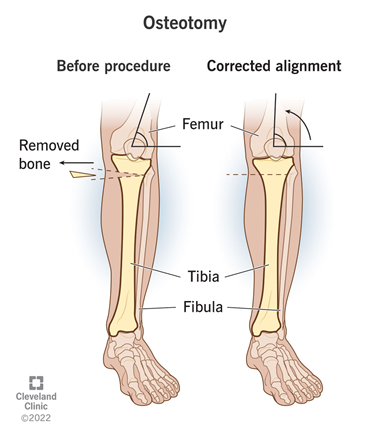

Surgery is often used as a last resort for osteoarthritis patients.2 The main procedures performed are osteotomies and partial or total joint replacement.1 Osteotomy is the surgical removal of a piece of bone.33 In the case of knee osteotomy, as shown by Figure 11, the surgeon might remove or add a piece of bone into the shin or thigh to shift weight to an undamaged portion of the joint, essentially correcting the joint alignment. There are several risks associated with osteotomy such as infections, blood clots, improper healing, joint inflammation, stiffness, and long term pain. It can also take a couple months for the surgical site to fully heal and will likely require supportive devices and physical therapy.34

Figure 11 Diagram of how knee osteotomy corrects joint alignment.34

This image shows an anatomical depiction of pre-osteotomy alignment and post-osteotomy corrected alignment.

Surgical options are the most costly and physically taxing. A knee osteotomy procedure typically costs around $20,000. Total and partial knee arthroplasties cost around $25,000 and hip arthroplasties cost around $20,000.41,42 Not only are these procedures expensive, the recovery time and process is much more extensive. Thus, surgery is often used as a last resort.2